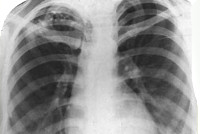

Основную информацию о форме туберкулеза дает рентгенография легких, однако рентгенологическая картина может быть различной в зависимости от фазы и длительности процесса. При свежем очаговом туберкулезе обычно определяется 1-2 крупных очага и несколько средних или мелких; тени слабоконтурирующие, малоинтенсивные, округлой формы. Хронический очаговый туберкулез рентгенологически проявляется наличием плотных фокусов с очагами обызвествления и фиброзных тяжей; тени средней и высокой интенсивности, обычно малого и среднего размера. Дифференциальная диагностика проводится с неспецифической очаговой пневмонией, пневмомикозами, периферическим раком легкого.

Туберкулиновые пробы при очаговом туберкулезе легких, как правило, малоинформативны, поэтому не играют важной диагностической роли. Для определения активности туберкулеза исследуется мокрота на КУБ, также производится бронхоскопия с забором бронхоальвеолярных смывов. Важное диагностическое значение принадлежит рентгенографическому исследованию легких и компьютерной томографии органов грудной клетки.